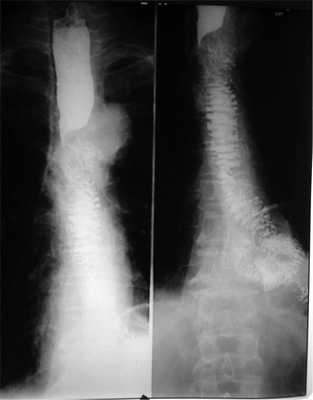

При контрольном обследовании через месяц после выписки из стационара, включающем рентгенографию органов грудной клетки и пищевода, ультразвуковое исследование брюшной полости и таза, данных о рецидиве и генерализации опухолевого процесса не выявлено. Пищеводно-тонкокишечный анастомоз находится в правой плевральной полости, стенки пищеводно-кишечного анастомоза гладкие, эластичные, эвакуация из пищевода не нарушена (см. рис. 1). Масса тела больного увеличилась на 4 кг, явлений дисфагии он не отмечает.

Рис. 1. Рентгенограмма внутриплеврального пищеводно-тонкокишечного анастомоза.